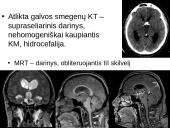

• Atlikta galvos smegenų KT – supraseliarinis darinys, nehomogeniškai kaupiantis KM, hidrocefalija.

MRT – darinys, obliteruojantis III skilvelį

• MRT – darinys, obliteruojantis III skilvelį